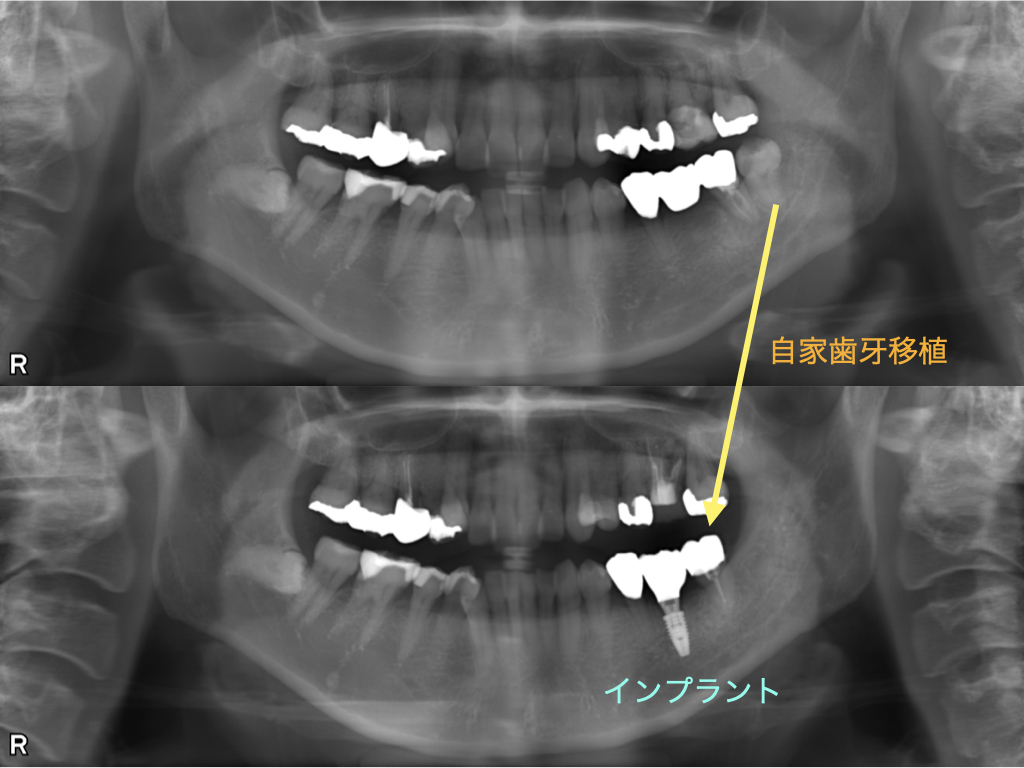

こちらの症例では、左下の奥歯2本を失った箇所に対し、以下の2つの異なるアプローチを行いました。

奥側(第2大臼歯部) 自家歯牙移植 親知らずを移植。歯根膜(クッション)を維持でき、自然な噛み心地が得られます。

手前側(第1大臼歯部) インプラント 移植できる自歯がない箇所に。周囲の健康な歯を削ることなく、強い咬合力を支えます。